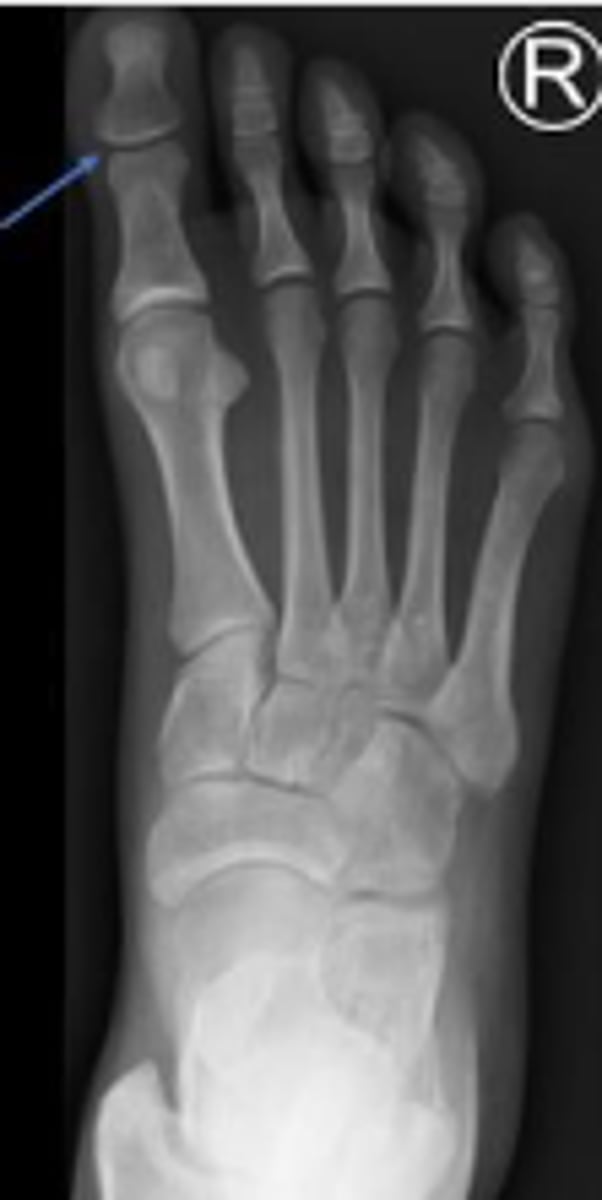

AP right foot

What is the name of the radiographic view?

Distal phalanx of the 1st digit of the right foot

What is outlined?

Middle phalanx of the 2nd digit of the right foot

Cuboid of the right foot

What are the arrows pointing to?

Interphalangeal joint of the 1st toe of the right

foot

What joint is the arrow pointing to?

Distal phalanx of the 3rd toe of the right foot

Medial cuneiform of the right foot

2nd metatarsal of the right foot

Sesamoid bones of the right foot within the tendon of the flexor hallicus brevis

Medial sesamoid of the right foot within the tendon of the flexor hallicus brevis